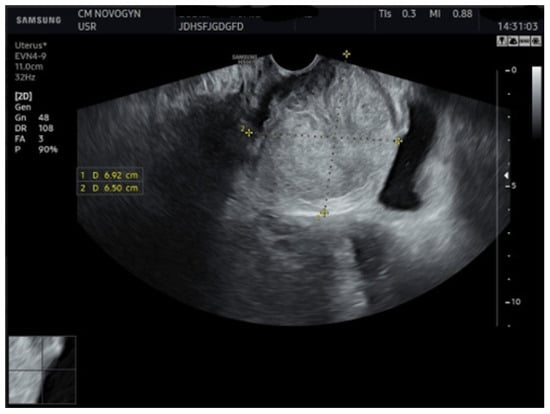

Initial transvaginal ultrasonography revealed a well-circumscribed, solid, predominantly hypoechoic mass measuring (6.9 × 6.5) cm located in the vesicovaginal region (Figure 1). The mass demonstrated homogeneous echotexture with well-defined borders and no internal cystic components. Color Doppler evaluation showed minimal internal vascularity. The uterus measured within normal limits, but demonstrated a fundal contour abnormality suggestive of septate uterus. Both ovaries appeared normal.

Given the patient’s young age and solid mass characteristics raising concern about malignancy, comprehensive magnetic resonance imaging (MRI) was performed using a 1.5-Tesla scanner with multiplanar sequences (General Electric, Cluj-Napoca, Romania). The MRI demonstrated signal intensity patterns highly suggestive of leiomyoma: isointense to muscle on T1-weighted imaging, markedly hypointense on T2-weighted imaging (characteristic of leiomyoma due to high fibrous content), restricted diffusion with high ADC values of 0.9 × 10−3 mm2/s (b-values: 0, 1000 s/mm2) consistent with benign leiomyoma, and homogeneous enhancement following gadolinium administration. In the literature [12], benign leiomyomas typically demonstrate ADC values in the range of 0.8–1.2 × 10−3 mm2/s, atypical leiomyomas may overlap, but are often slightly lower (0.7–1.0 × 10−3 mm2/s), while leiomyosarcomas tend to show more pronounced restriction, often <0.8 × 10−3 mm2/s. These ranges overlap, highlighting that although MRI provides highly suggestive features, histopathological confirmation remains essential. MRI also confirmed the septate uterus and showed detailed anatomical relationships (Figure 3 and Figure 4).